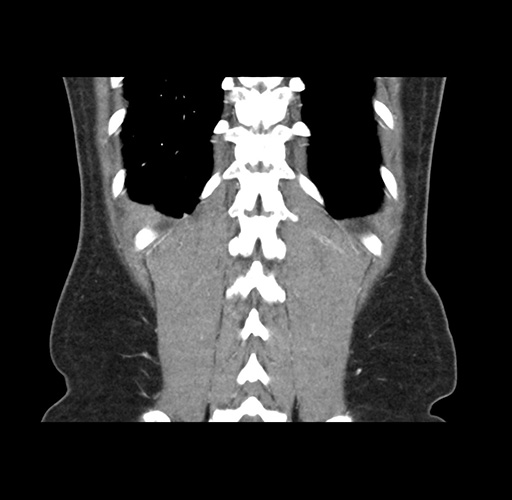

Imaging Analysis

Look through the patient's CT scan to identify any areas of concern for the necessary procedure.

Based on your CT findings, which issue(s) would give reason for "planned slowing down moment(s)" in this case?